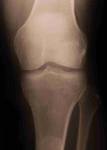

Used

with permission from Ross A Hauser, MD,

www.caringmedical.com.

Historical review shows

that a version of this technique was first used by

Hippocrates on soldiers with dislocated, torn shoulder

joints. He would stick a hot poker into the joint, and it

would then miraculously heal normally. Of course, we don’t

use hot pokers today, but the principle is similar—get the

body to repair itself, an innate ability that the body

has.